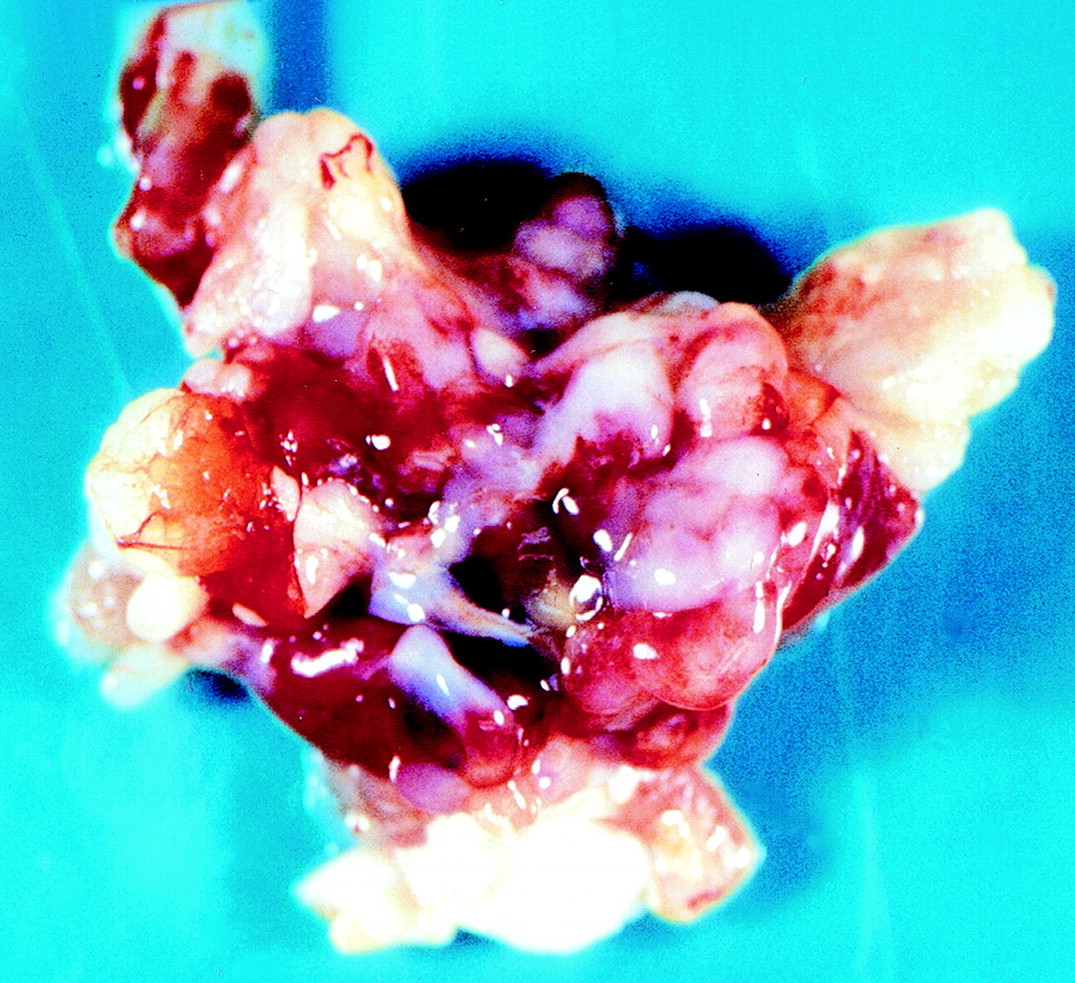

Патологическая анатомия. Миксома представляет собой солитарное, реже множественное новообразование округлой или овальной формы, не распространяющееся далее субэндокардиальных слоев сердца. Макроскопически миксомы имеют две разновидности: первая - полупрозрачная, бесцветнаяжелатинозная по консистенции, фиксированная к стенке сердца более или менее широким основанием; вторая - округлая плотная масса, свисающая на ножке (80%). Внешний вид опухоли напоминает полип или виноградную гроздь диаметром от 5 мм до 8 -12 см с крупно-или мелкозернистой поверхностью, масса ее может достигать 250 г. Поверхность опухоли блестящая, капсула отчетливо выражена. Цвет может Рис. 61. Первичные опухоли сердца (по F. Netter, 1969, с изменениями) Рис. 62. ЭхоКГ миксомы правого предсердия (В-режим) варьировать от зеленовато-серого до желтовато-коричневого, опухоль желеобразной или значительно реже эластической консистенции. В самой опухоли могут обнаруживаться дистрофические изменения - некрозы , кровоизлияния, реже происходит обызвествление.